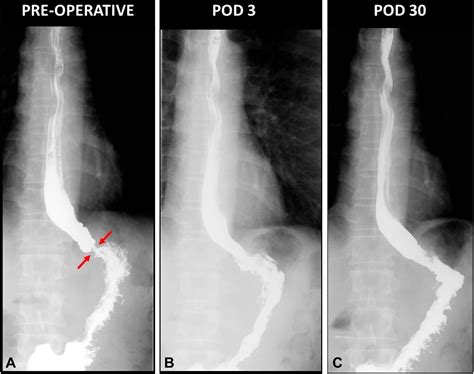

• Barium Swallow: This test involves swallowing a barium solution, which coats the esophagus and makes it visible on X-rays. Any narrowing or abnormalities can be identified.